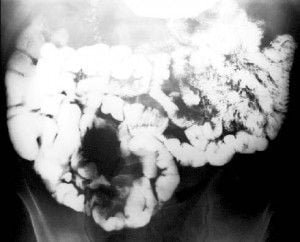

Abdomen, aparato digestivo y via biliarTécnicas de Exploración Radiológica Tránsito del intestino delgado Parte II 28 junio, 2012 Tidito Transito intestinal contraste simple Transito intestinal doble contraste yeyuno e ileon Patologia de Transito intestinal – Enfermedad celiaca Tumor maligno ileon terminalEnfermedad inflamatoria intestinal